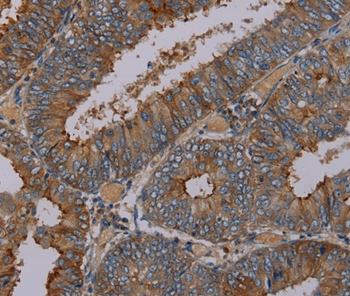

Immunohistochemical analysis of paraffin-embedded Human colon cancer tissue using #37813 at dilution 1/30.